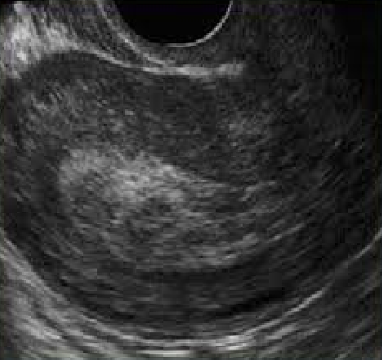

¿Qué hallazgos ecográficos confirman una gestación normal en amenaza de aborto?

Gestación con características normales.

¿Qué es un huevo anembrionado?

Saco gestacional intrauterino mayor a 25 mm sin embrión ni saco vitelino, confirmado por **dos ecografías** con 7-14 días de diferencia.

Detención del desarrollo ovular con retención del saco gestacional o feto, sin vitalidad en ecografía.

¿Qué hallazgos ecográficos confirman un huevo muerto y retenido?

- Ausencia de vitalidad - Lisis embrionaria - Saco gestacional deformado - Hematomas retrocoriales/placentarios